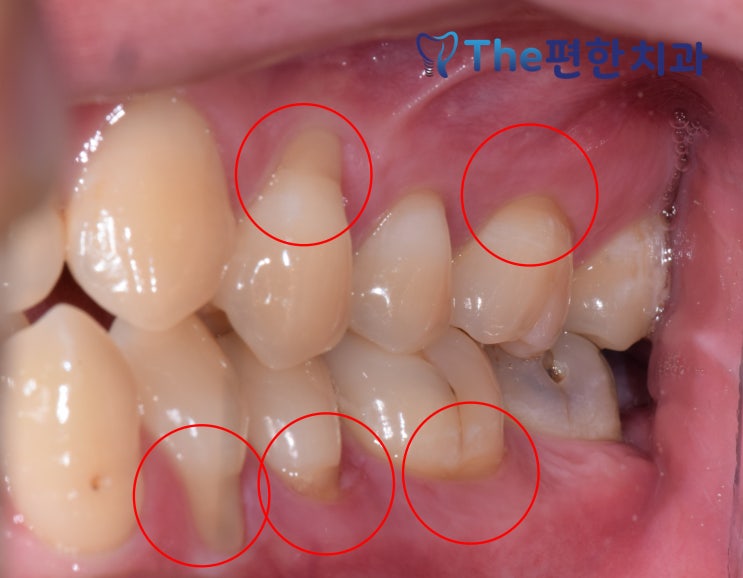

수완지구, 장덕동 더편한치과 충치치료 더 꼼꼼하게 합니다.